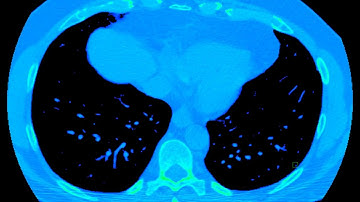

SST076: Lung Cancer Classification using CT Scan Image Data based on GLCM and ELM